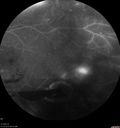

PDR and Vitreous Hemorrhage - High Risk Left Eye - Low Risk Right Eye

50 year old man with type I diabetes mellitus for 26 years. New Vitreous Hemorrhage in the left eye. Both eyes have NVE. Both also have foveal hypoplasia